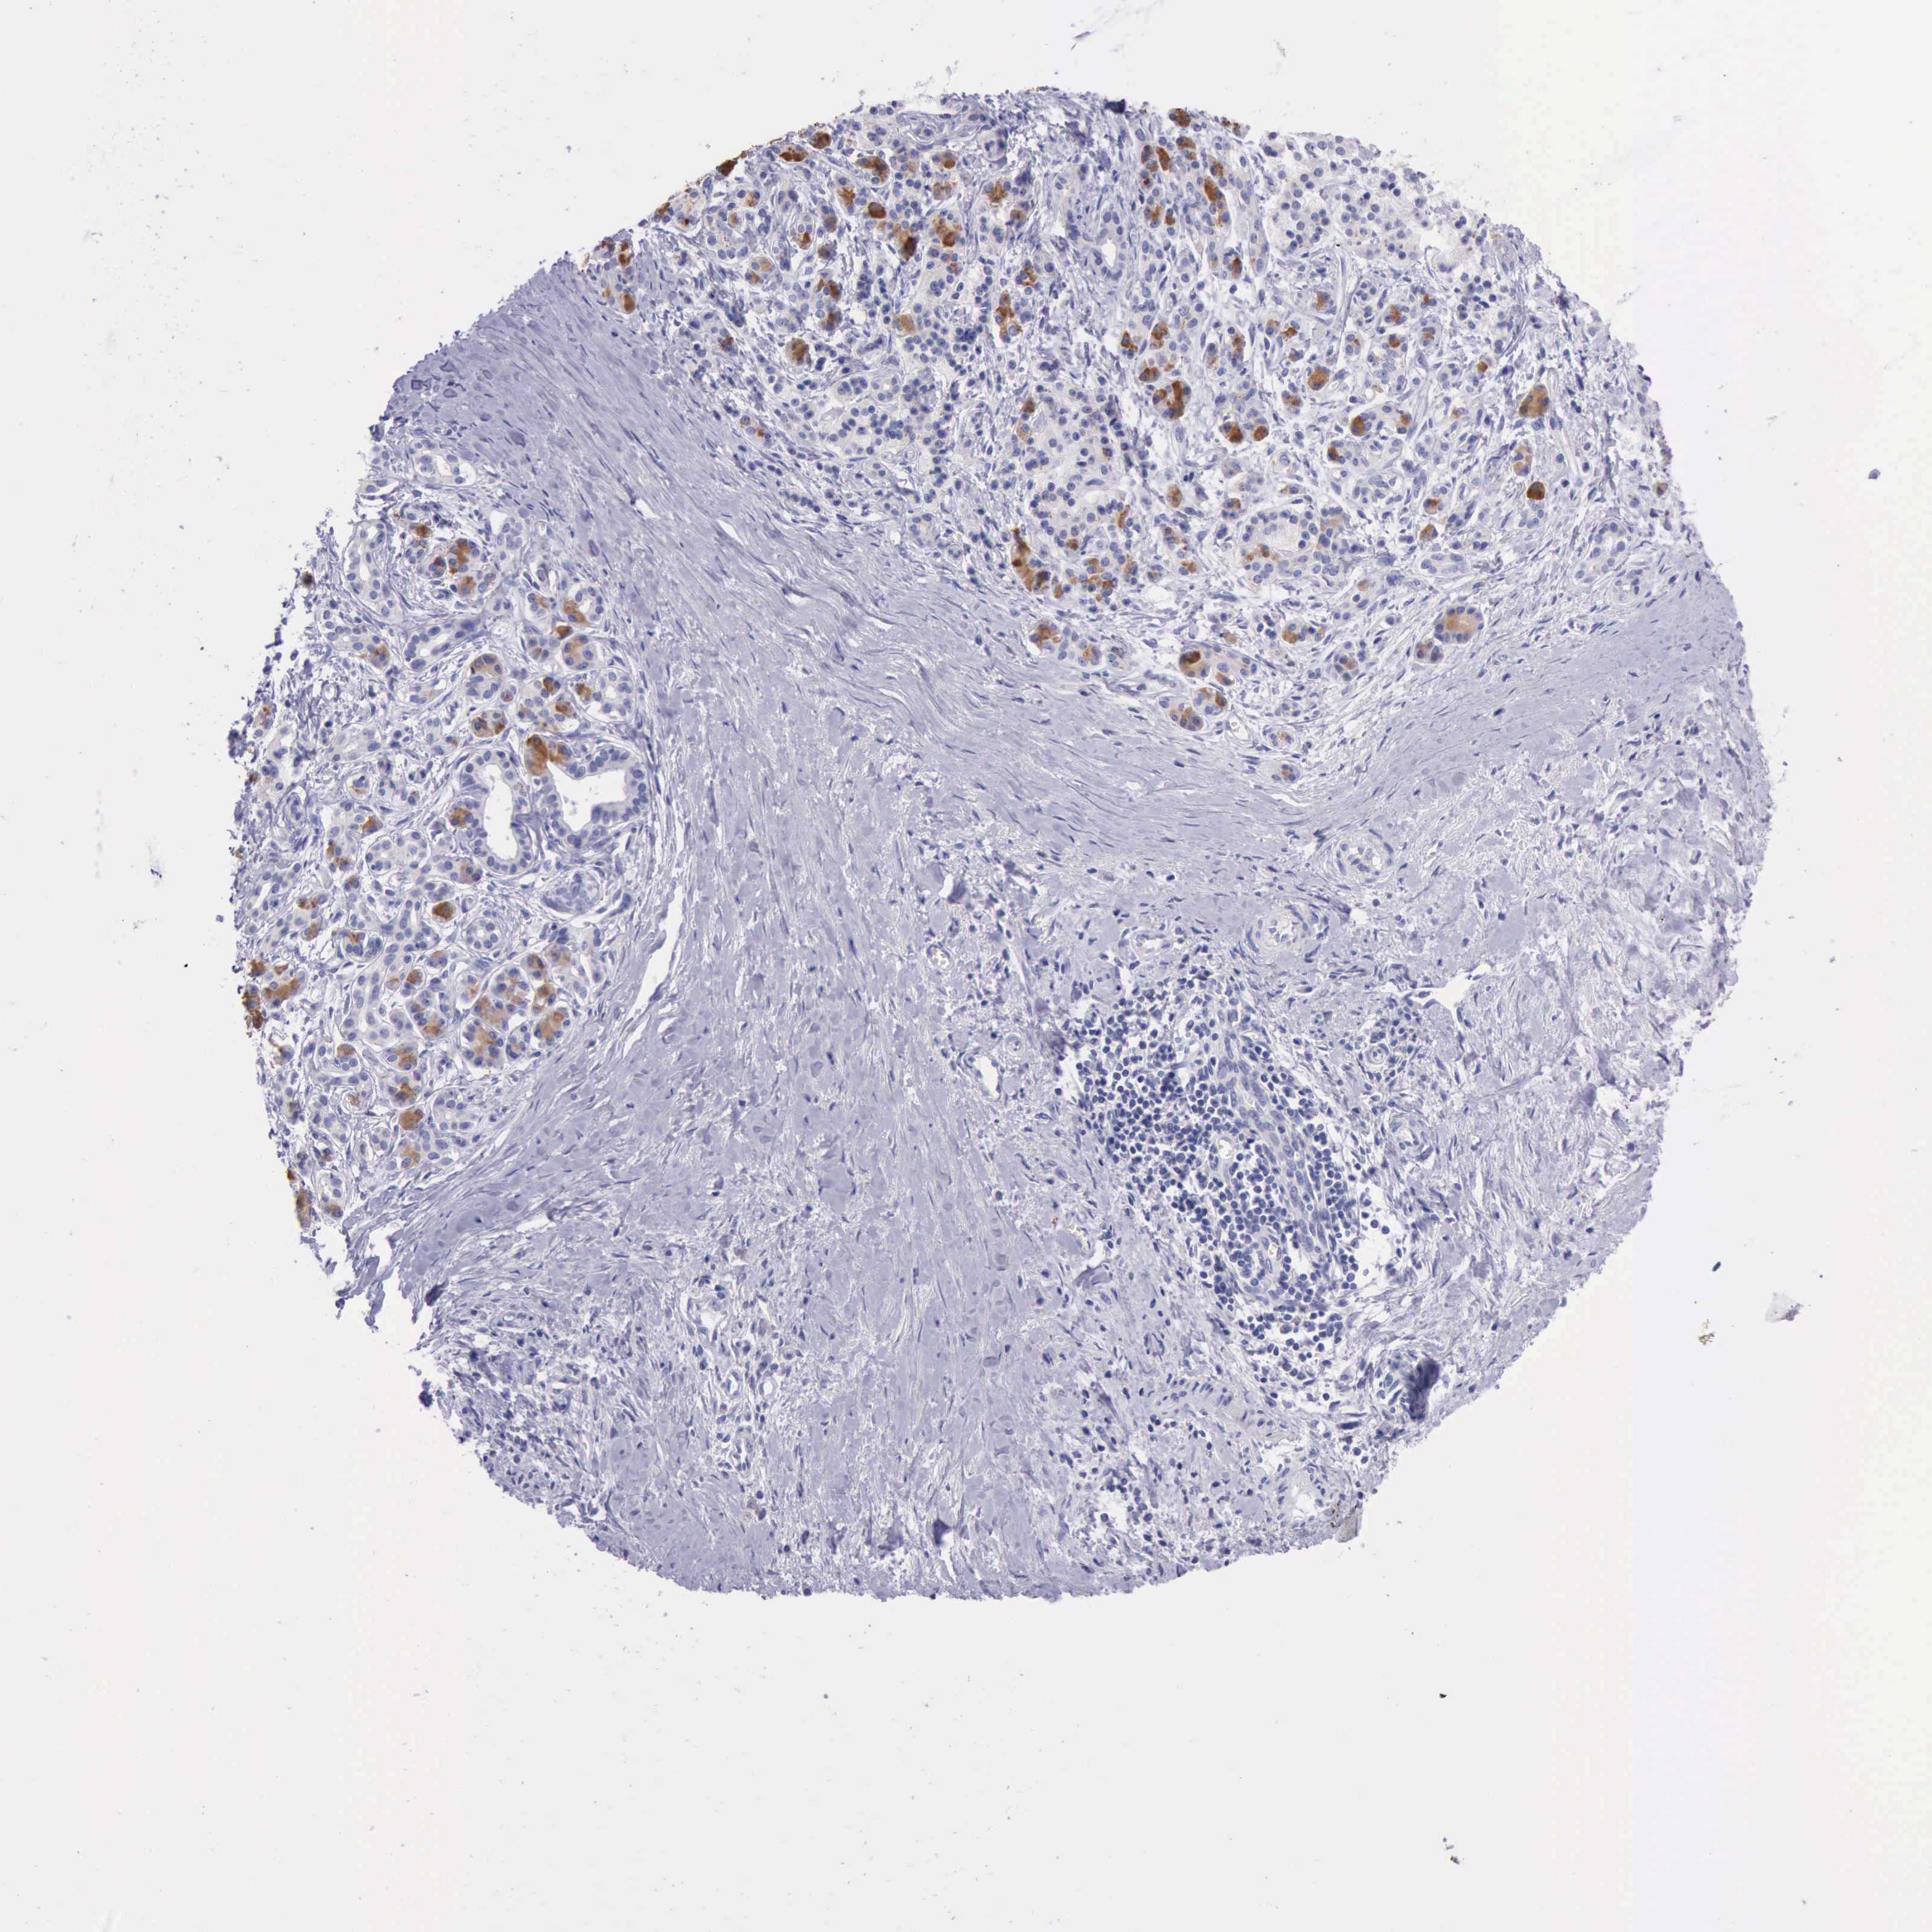

PANCREATIC CANCER - Protein expressioni

A mouse-over function shows sample information and annotation data. Click on an image to view it in a full screen mode. Samples can be filtered based on level of antibody staining by selecting one or several of the following categories: high, medium, low and not detected. The assay and annotation is described here.

Note that samples used for immunohistochemistry by the Human Protein Atlas do not correspond to samples in the TCGA dataset.

Antibody stainingi

Antibody staining in the annotated cell types in the current human tissue is reported as not detected, low, medium, or high, based on conventional immunohistochemistry profiling in selected tissues. This score is based on the combination of the staining intensity and fraction of stained cells.

Each image is clickable and will lead to virtual microscopy that enables deeper exploration of all samples and also displays staining intensity scores, fraction scores and subcellular localization as well as patient and tissue information for each sample.

Antibody HPA001177

Staining

High

Medium

Low

Not detected

Intensity

Strong

Moderate

Weak

Negative

Quantity

>75%

75%-25%

<25%

None

Location

Nuclear

Cytoplasmic/membranous

Cytoplasmic/membranous,nuclear

Adenocarcinoma, NOS